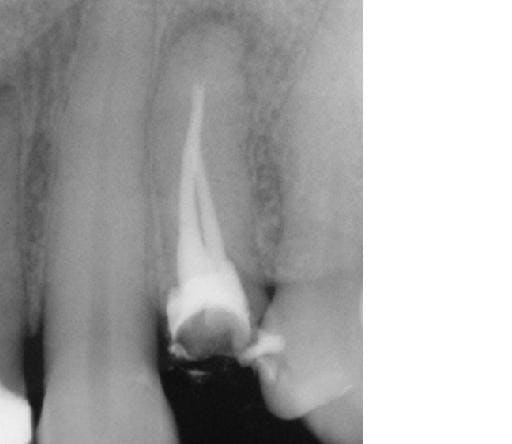

celle la faudra me dire comment on passe sans laser (et comment on y injecte autre chose que de la pate).

sinon: micjhel costeseque obture cortisomol lentulo+laser et ensuite maitre cone gutta (je l'ai vu y'a 15 jours).

le risque pate seule est qu'elle est trés trés compacte et dure.... pas gai pour une reprise de traitement et donc pate seule pour les 2 derniers mm mais cone foulé à chaud ensuite (je sais je faisais pas comme ça "avant" mais j'ai écouté les copains d'eugenol et me suis remis à la gutta.... par contre la digue....).

photo lime en place: pas possible aller + loin même en manuel avec une n°8....

1ere endo: lentulo pate trés fluide

2eme: premier tir et relentulo (pate trés fluide poussée par le laser et + épaisse pour la deuxiéme couche au lentulo)

3eme: deuxieme tir (je voulais chopper les 2 racines....) et relentulo et gutta.

ps: cette dent était donnée pour perdue et la seule proposition faite à la patiente était implant.... (idem pour la 22 qui est certes à refaire/reprendre mais sans doute pas perdue....)

y m'a fallu 30 minutes pour desobturer et réobturer, Sc33 sur tenoçns titane et coiffe provisoire posées cet aprtés midi, endo faite y'a 2 jours et RAS.